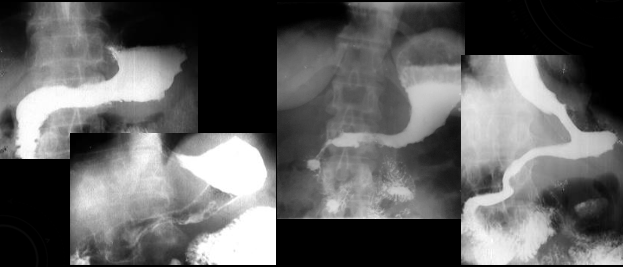

Neoplasm malign gastric vegetant

Neoplasm malign gastric infiltrativ

Neoplasm malign gastric ulcerant

Neoplasm malign gastric ulcero-vegetant